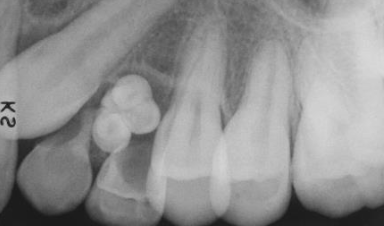

Calcifying epithelial odontogenic tumor (CEOT) - 下顎 30-50y

• 類似 Ameloblastoma,可能單多囊

• 鈣化,長得慢,低侵略,邊界清楚

• 阻生齒

• 復發率約 15%